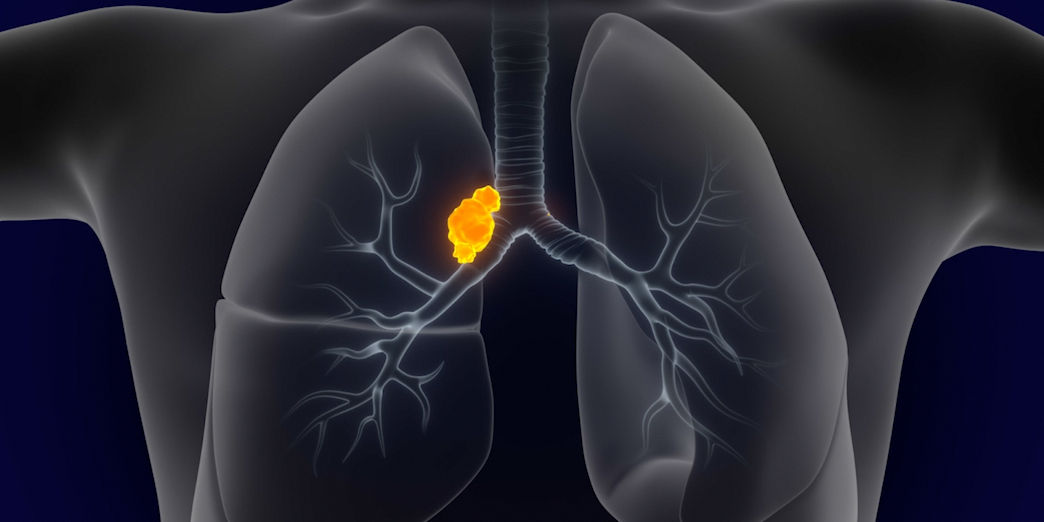

Learn about expanding options to delay relapse after induction.

1L TREATMENT- Rudin CM, Brambilla E, Faivre-Finn C, Sage J. Small-cell lung cancer. Nat Rev Dis Primers. 2021;7(1):3. doi:10.1038/s41572-020-00235-0

- Byers LA, Rudin CM. Small cell lung cancer: where do we go from here? Cancer. 2015;121(5):664-672.

- Huber RM, Tufman A. Update on small cell lung cancer management. Breathe. 2012;8(4):314-330.

- Small cell lung cancer stages. American Cancer Society. https://www.cancer.org/cancer/lung-cancer/detection-diagnosis-staging/staging-sclc.html. Accessed March 25, 2025.